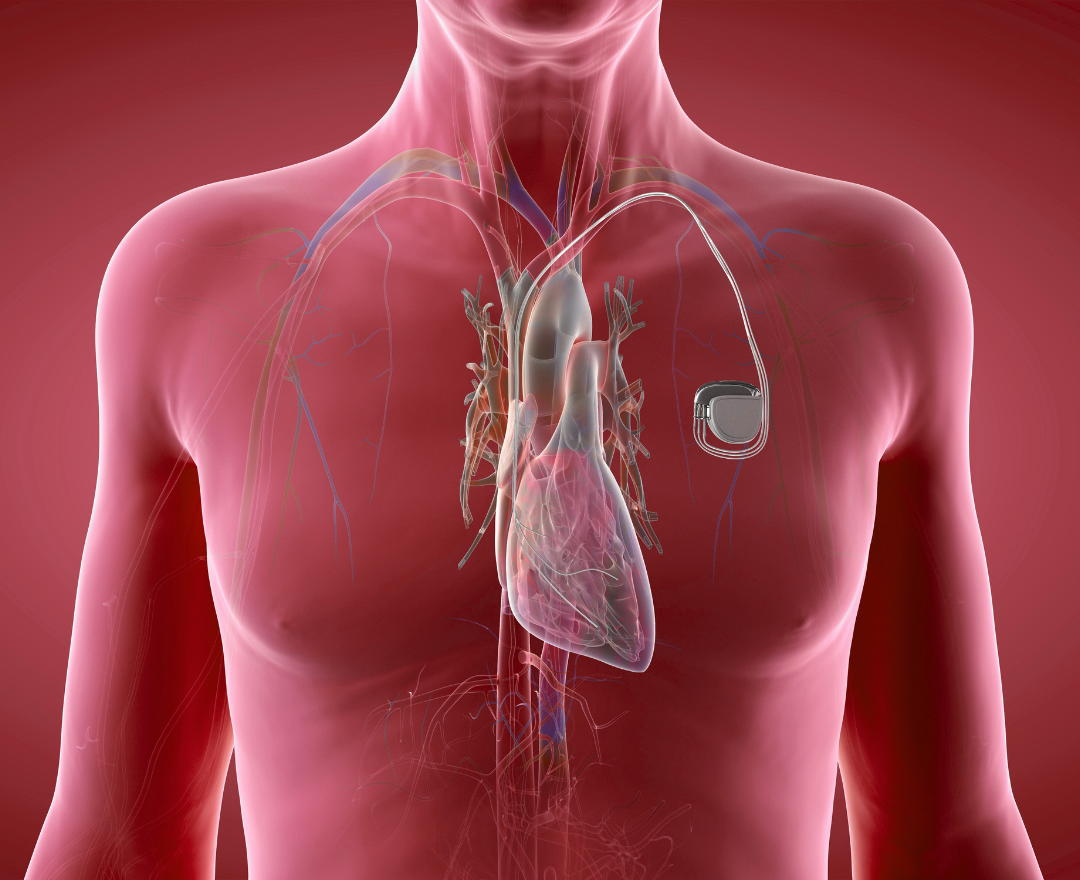

O marcapasso é um dispositivo pequeno, mas essencial, para corrigir batimentos cardíacos lentos ou irregulares.